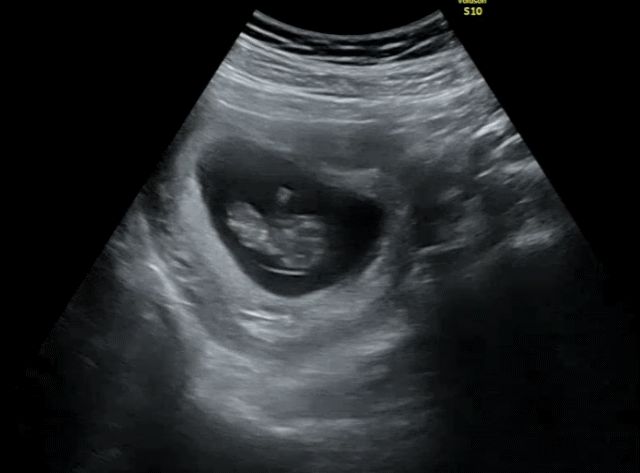

저는 갔는데 자고 있는지 움크려있었어요 ㅎㅎ 심장소리 173으로 아주 건강하다구 해서 안심했어요

10주차 초음파

입덧 때문에 일상생활도 제대로 못하던 와중 반디는 건강하게 잘자라고 있었나봐요 주수에 맞게 잘자라고 있고 초음파 보자마자 갓잡은 생선처럼 팔딱팔딱 튀는데 다른 분들도 이런가요? 이 정도면 많이 활발한 편인지 궁금합니다